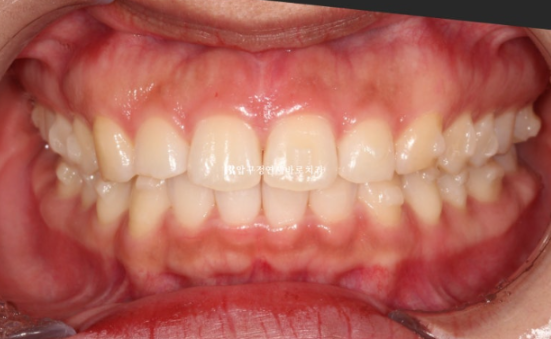

24.10

24.02~24.10

뻗쳐있던 앞니 각도는 좋아졌고

공간도 깔끔하게 모아졌으며 배열도 좋습니다.

앞니를 뒤로 넣을 때 단순 뒤로만 움직이는 것이 아니라 위로 올리면서 함입하며 넣었기에 잇몸 노출량도 소량 줄었습니다.

일자로 떨어지는 앞니 각도는 세련된 인상을 줍니다